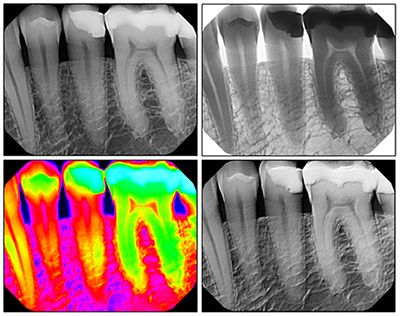

Digital X-Rays

We have introduced new digital x-rays as part of our effort to provide the safest treatment possible to our patients. Digital x-rays transmit 95% less radiation than traditional dental x-rays, and feature smaller, more comfortable sensors. Currently, our office features Digital Panorex full-face imaging. This technology allows for more accurate treatment and communication with dental specialists. The Digital Panorex can pick up unseen medical conditions and help our team make a comprehensive diagnosis.

Our practice uses the KaVo DIAGNOdent® laser to detect tooth decay in its earliest stages. The DIAGNOdent® laser is currently the most accurate detection tool available to dentists, and can uncover decay that would go unnoticed by traditional methods of diagnosis. With the DIAGNOdent® laser, our team can assist patients in preventing future problems and maintaining optimum oral health.